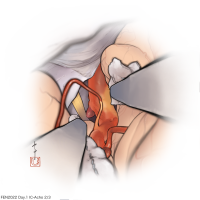

監修:谷川 緑野 / 札幌禎心会病院脳卒中センター

FEN2022シリーズ

術後イラストシリーズ